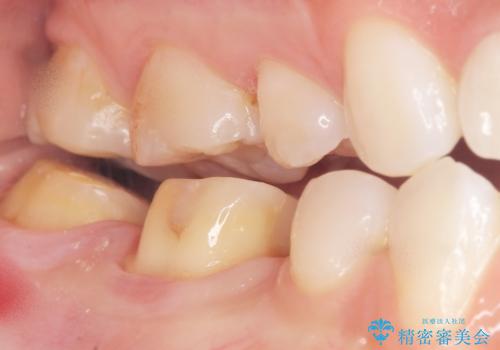

矯正せずに隙間を閉じることができ、ご満足頂けました。

セラミッククラウンの審美的な仕上がりと咬み心地に喜んで下さいました。

クラウンの種類:オールセラミッククラウン スタンダード